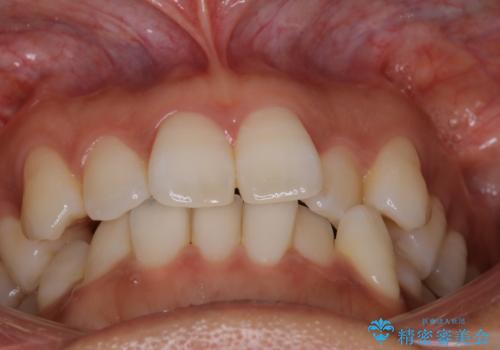

【インビザライン】前歯をきれいな歯並びにしたい

- 前歯の叢生を主訴に来院されました。このケースは抜歯をせずにIPRにてスペースを確保し、並べる計画をたてました。

きちんと使用時間を守って使用していただいたことで短い期間で治療が終了しました。